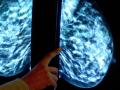

La plupart des femmes atteintes d'un cancer du sein au stade précoce peuvent être en mesure d'...